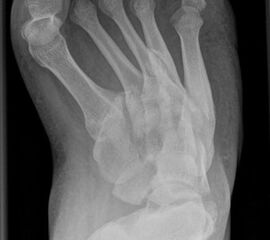

Biomechanische Überlegungen zum direkten Hohlfuß

Der direkte Hohlfuß zeigt im gesamten Vorfuß durch die steilgestellten Metatarsalia I-V nicht nur eine Betonung der Vorfuß-Equinusstellung mit schmerzhafter plantarer Beschwielung aller Metatarsaliaköpfe, sondern auch eine transversale Verbreiterung (Spreizung) der distalen Metatarsalia und Phalangen. Eine Inversion des Rückfußes kann durch zusätzliche Dysbalancen gelegentlich konsekutiv entstehen.

Da der balancierende Effekt der intrinsischen Muskulatur ausbleibt, welcher die Grundphalangen plantarflektieren würde, zieht die übermächtige extrinsische Muskulatur (M. extensor digitorum longus) infolge ihrer Ansätze an den Endphalangen die Grundphalangen in die ungehinderte Hyperdorsalextension. Wie eine Ziehharmonika wird der Vorfuß dem Rückfuß angenähert (Abb. 20). Es bildet sich eine Klauenzehendeformität. Die Metatarsaleköpfe werden in die Plantarflexion „geschoben“. Der Drehpunkt der Bewegungsachse der Grundgelenke verschiebt sich nach plantar und selbst die langen Flexoren (M. flexor digitorum longus) fungieren als Dorsalextensoren des Grundgliedes und verstärken die Deformität.

Die verstärkte Aufspreizung des Vorfußes resultiert ebenfalls aus der Schwächung der intrinsischen Muskulatur, welche in normaler Funktion auch eine transversale Verspannung der distalen Metatarsalia bewirkt. Die intermetatarsal verlaufenden Anteile der M. interossei ermöglichen eine aktive Verspannung zwischen den einzelnen Metatarsalia.

Durch Schwächung der intrinsischen Grundgliedflexoren entstehen flexible, später kontrakte Klauenzehen.